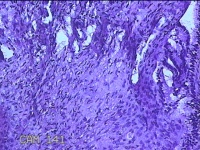

宫颈赘生物

性别

女

年龄

38岁

临床诊断

稽留流产

一般病史

停经2月余,阴道流血5天。

标本名称

大体所见

灰白粉红色不规则肿物1.5x1.2x0.3cm两个,表面糜烂,切开肿物呈实性,切面灰白粉红色,质软。

有可能调整一下拍照,部分区域看不清